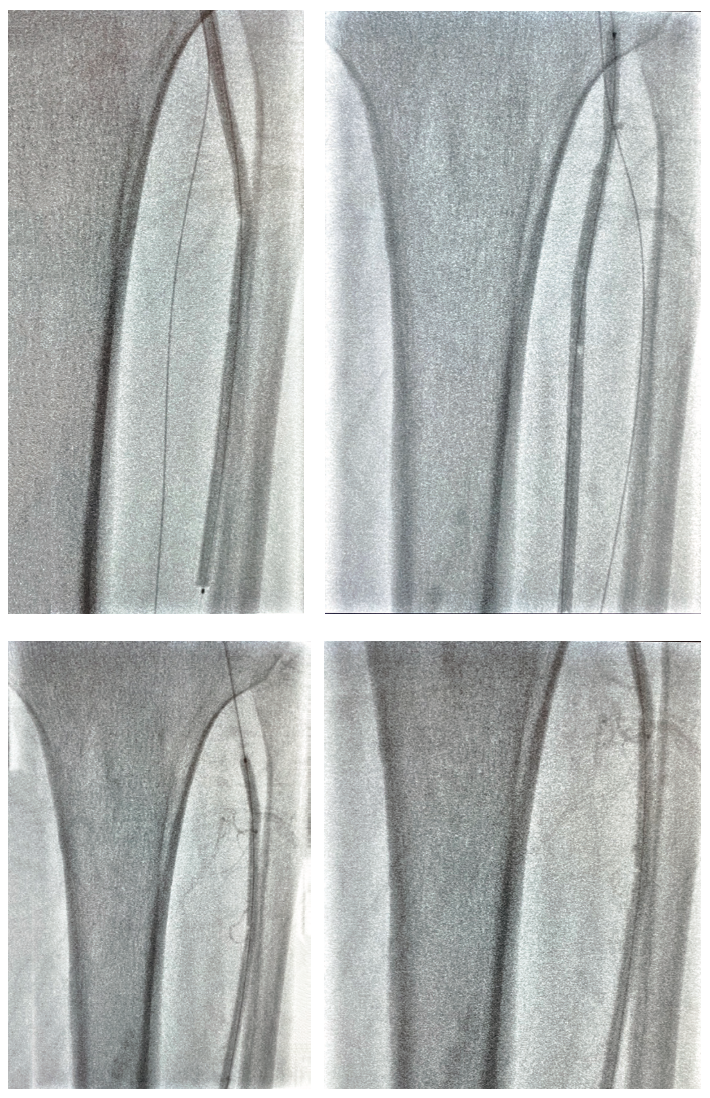

Inflow in the popliteal was optimized with plain balloon angioplasty (POBA) prior to addressing the BTK lesions (Figure 2). A 3 mm x 120 mm Serranator PTA Serration Balloon Catheter (Cagent Vascular) was utilized with serial overlapping inflations to treat the anterior tibial artery. The Serranator was used distal to proximal with max inflation at 12 atmospheres (atm) for two minutes (Figures 3-4). A 3 mm x 80 mm Serranator balloon was then used in a similar manner to treat the TPT, with a maximum inflation of 8 atm for two minutes. Following Serranator use, significant lumen gain and improved flow was observed, with 0% stenosis and no dissection, perforation, or recoil noted (Figure 5).